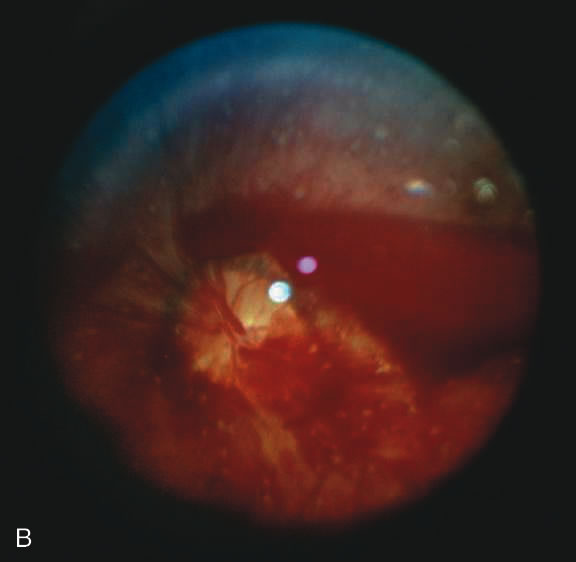

Findings range from a normal fundus to a small number of scattered intraretinal hemorrhages in the posterior pole to massive, confluent hemorrhages from the posterior pole to the ora serrata.(Fig. 10) The hemorrhages may be subretinal, deep intraretinal (dot/blot), nerve fiber layer (flame shaped) or preretinal.19,45 Intraretinal hemorrhages are more common than preretinal or subretinal hemorrhages.32,46 Preretinal hemorrhages must be distinguished from traumatic retinoschisis (see later), which has particular diagnostic significance. White-centered retinal hemorrhages, although classically associated with endocarditis, can occur in any condition that causes retinal hemorrhages, including SBS. Vitreous hemorrhage may be small to massive, and may occur secondary to escape of blood from intraretinal collections or from torn vessels.19 Although vitreous hemorrhage may occur at the time of injury, it may also be a delayed finding occurring 1 to 3 days or more after the initial trauma.47,48

Fig. 10. Retinal hemorrhages in SBS may range from a nonspecific mild posterior pole distribution (10A) to a more characteristic picture of too numerous to count, multiple, extensive intraretinal hemorrhages (in this many with white centers) with subhyaloid hemorrhage (10B, 10C)

The differential diagnosis of retinal hemorrhages in a child is vast. However, if one considers a child with the full spectrum of injuries seen in SBS, including brain, skeletal, and eye findings, most would not dispute that the retinal findings are due to nonaccidental injury. However, in a child with a small number of retinal hemorrhages and without retinoschisis, (Fig. 10A) the diagnosis of SBS may be less clear.